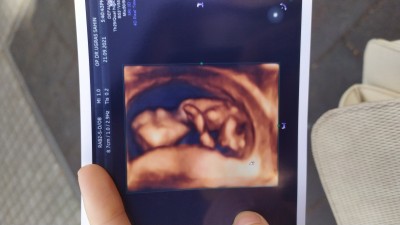

15 Ekim 2021 Hamilelik Dönemi Genel kategorisinde (4 puan) sordu

İlk 12 haftalıkken kız dedi doktorum. İkinci kez erkek dedi ama kesin deil dedi . Şuan 16+4 haftaligim bugünde gittim kesin bişey demedi bebeğim bacak arasını kapatıyor göstermiyor .

Gebelik haftası 16+4